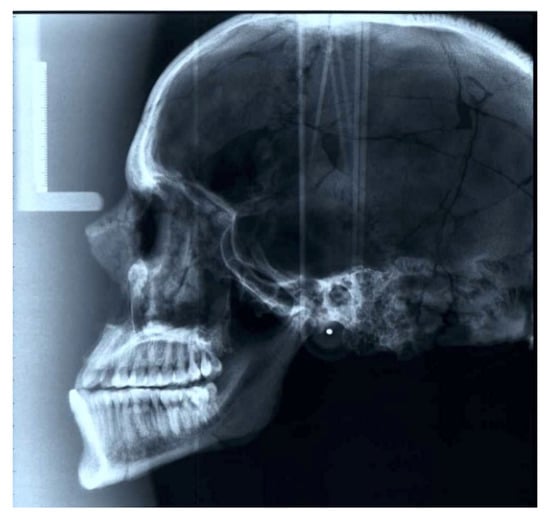

No pathological lesions were recorded, macroscopically, except for a slight porosis in the bregmatic area. The findings from the endoscopic analysis did not show any intra vitam lesions, but severe diagenesis was diagnosed in almost all areas of the endocranium and the orbital laminae. However, two noteworthy findings were remarked in the X-rays. In the X-ray of the long bones, Harris lines, or growth arrest lines, were visible (Figure 4). Furthermore, in the skull X-ray, a hair-on-end pattern was noted, especially around the lambda point, along with a widening of the diploic space (Figure 5). Signs of pitting edema were suggested around the bregmatic areas of the skull.

Regarding radiographic findings, the diploic hair-on-end sign seen in the skull X-ray is usually due to the overactivity of the red bone marrow in response to anemia and blood disorders [56]. Skull abnormalities in patients with anemia are produced by cellular hyperplasia, circulatory factors, or a combination of both. The lesions caused by red marrow hyperplasia, such as the expansion of the diploe, thinning of the outer table, and vertical trabeculations, have been described by investigators in patients with thalassemia major, iron deficiency anemia, sickle cell disease, and spherocytosis [56]. The mild porotic hyperostosis that was noted also implies anemia, though recent findings have also suggested potential hemolytic and megaloblastic anemias [57]. Furthermore, Harris lines, as noticed on the long bones, are commonly a result of malnutrition, disease, or trauma [58]. All these signs seem to complete the puzzle of the diagnosis, so that we can reasonably assume that Avgi suffered from iron deficiency anemia due to iron malabsorption or malnutrition.

In the X-ray profile of the Theopetra skull, the feature of the hair-on-end may not actually present the outgrowth of the diploic trabeculae at the expense of the disintegration of the external lamina, but rather a localized diagenetic effect of the sagittal and lambdoid sutures, due to the severe diagenesis diagnosed in the endoscopic investigation [64]. However, it is imperative to attempt a differential diagnosis, since the reliability of findings in paleopathological studies of ancient bones demands complementary levels of analysis. It should be noted that the hyperplasia of marrow may also be a sign of lead poisoning and cyanotic heart disease. In this perspective, the stage at which iron deficiency is manifested in the skeleton and the pathway to iron deficiency anemia is not traceable with high credibility in the ancient bones and depends on dietary factors. Furthermore, the association of iron deficiency anemia with infectious factors is documented, involving the protein hepcidin [65] or the bacterium Clostridium botulinum found in honey [66]. Relatively recent data complicate the diagnosis even more, with studies documenting a genetic predisposition for iron deficiency anemia in some groups with high iron intake and uptake [67].

Figure 5. Lateral cephalometric radiograph of the skull.